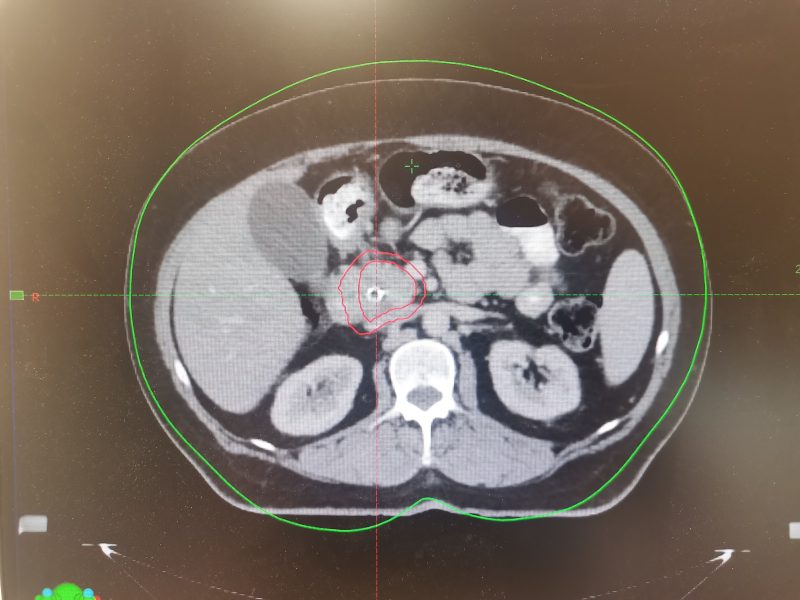

Клинический пример: Пациентка 67 лет с неоперабельным раком головки поджелудочной железы.

В начале 2023г обратилась в больницу с жалобами на боли в эпигастрии, желтушность кожных покровов и склер глаз. При обследовании выявлена опухоль размерами 32х22 мм, которая сдавила желчные протоки, нарушила отток желчи и привела к развитию желтухи. Опухоль признана неоперабельной. Пациентке хирургическим путем установлен стент. Назначены курсы лекарственной терапии, которые привели к стабилизации процесса. На консилиуме было принято решение провести стереотаксическую лучевую терапию для уменьшения размеров опухоли. После КТ-топометрии на задержке дыхания выполнено оконтуривание и физико-дозиметрический расчет. Проведено 5 сеансов СТЛТ под ежедневным контролем укладки лечащим врачом-радиотерапевтом и медицинским физиком. Контроль мишени осуществлялся совмещением снимков пациентки в реальном времени со сканами КТ-топометрии. В процессе лечения и после его окончания побочных эффектов не отмечено. На контрольном МРТ через 3 месяца- выраженный лечебный эффект (опухоль не визуализируется). В настоящий момент женщина находится в процессе лекарственной терапии.

Январь 2023 года. Март 2026 года